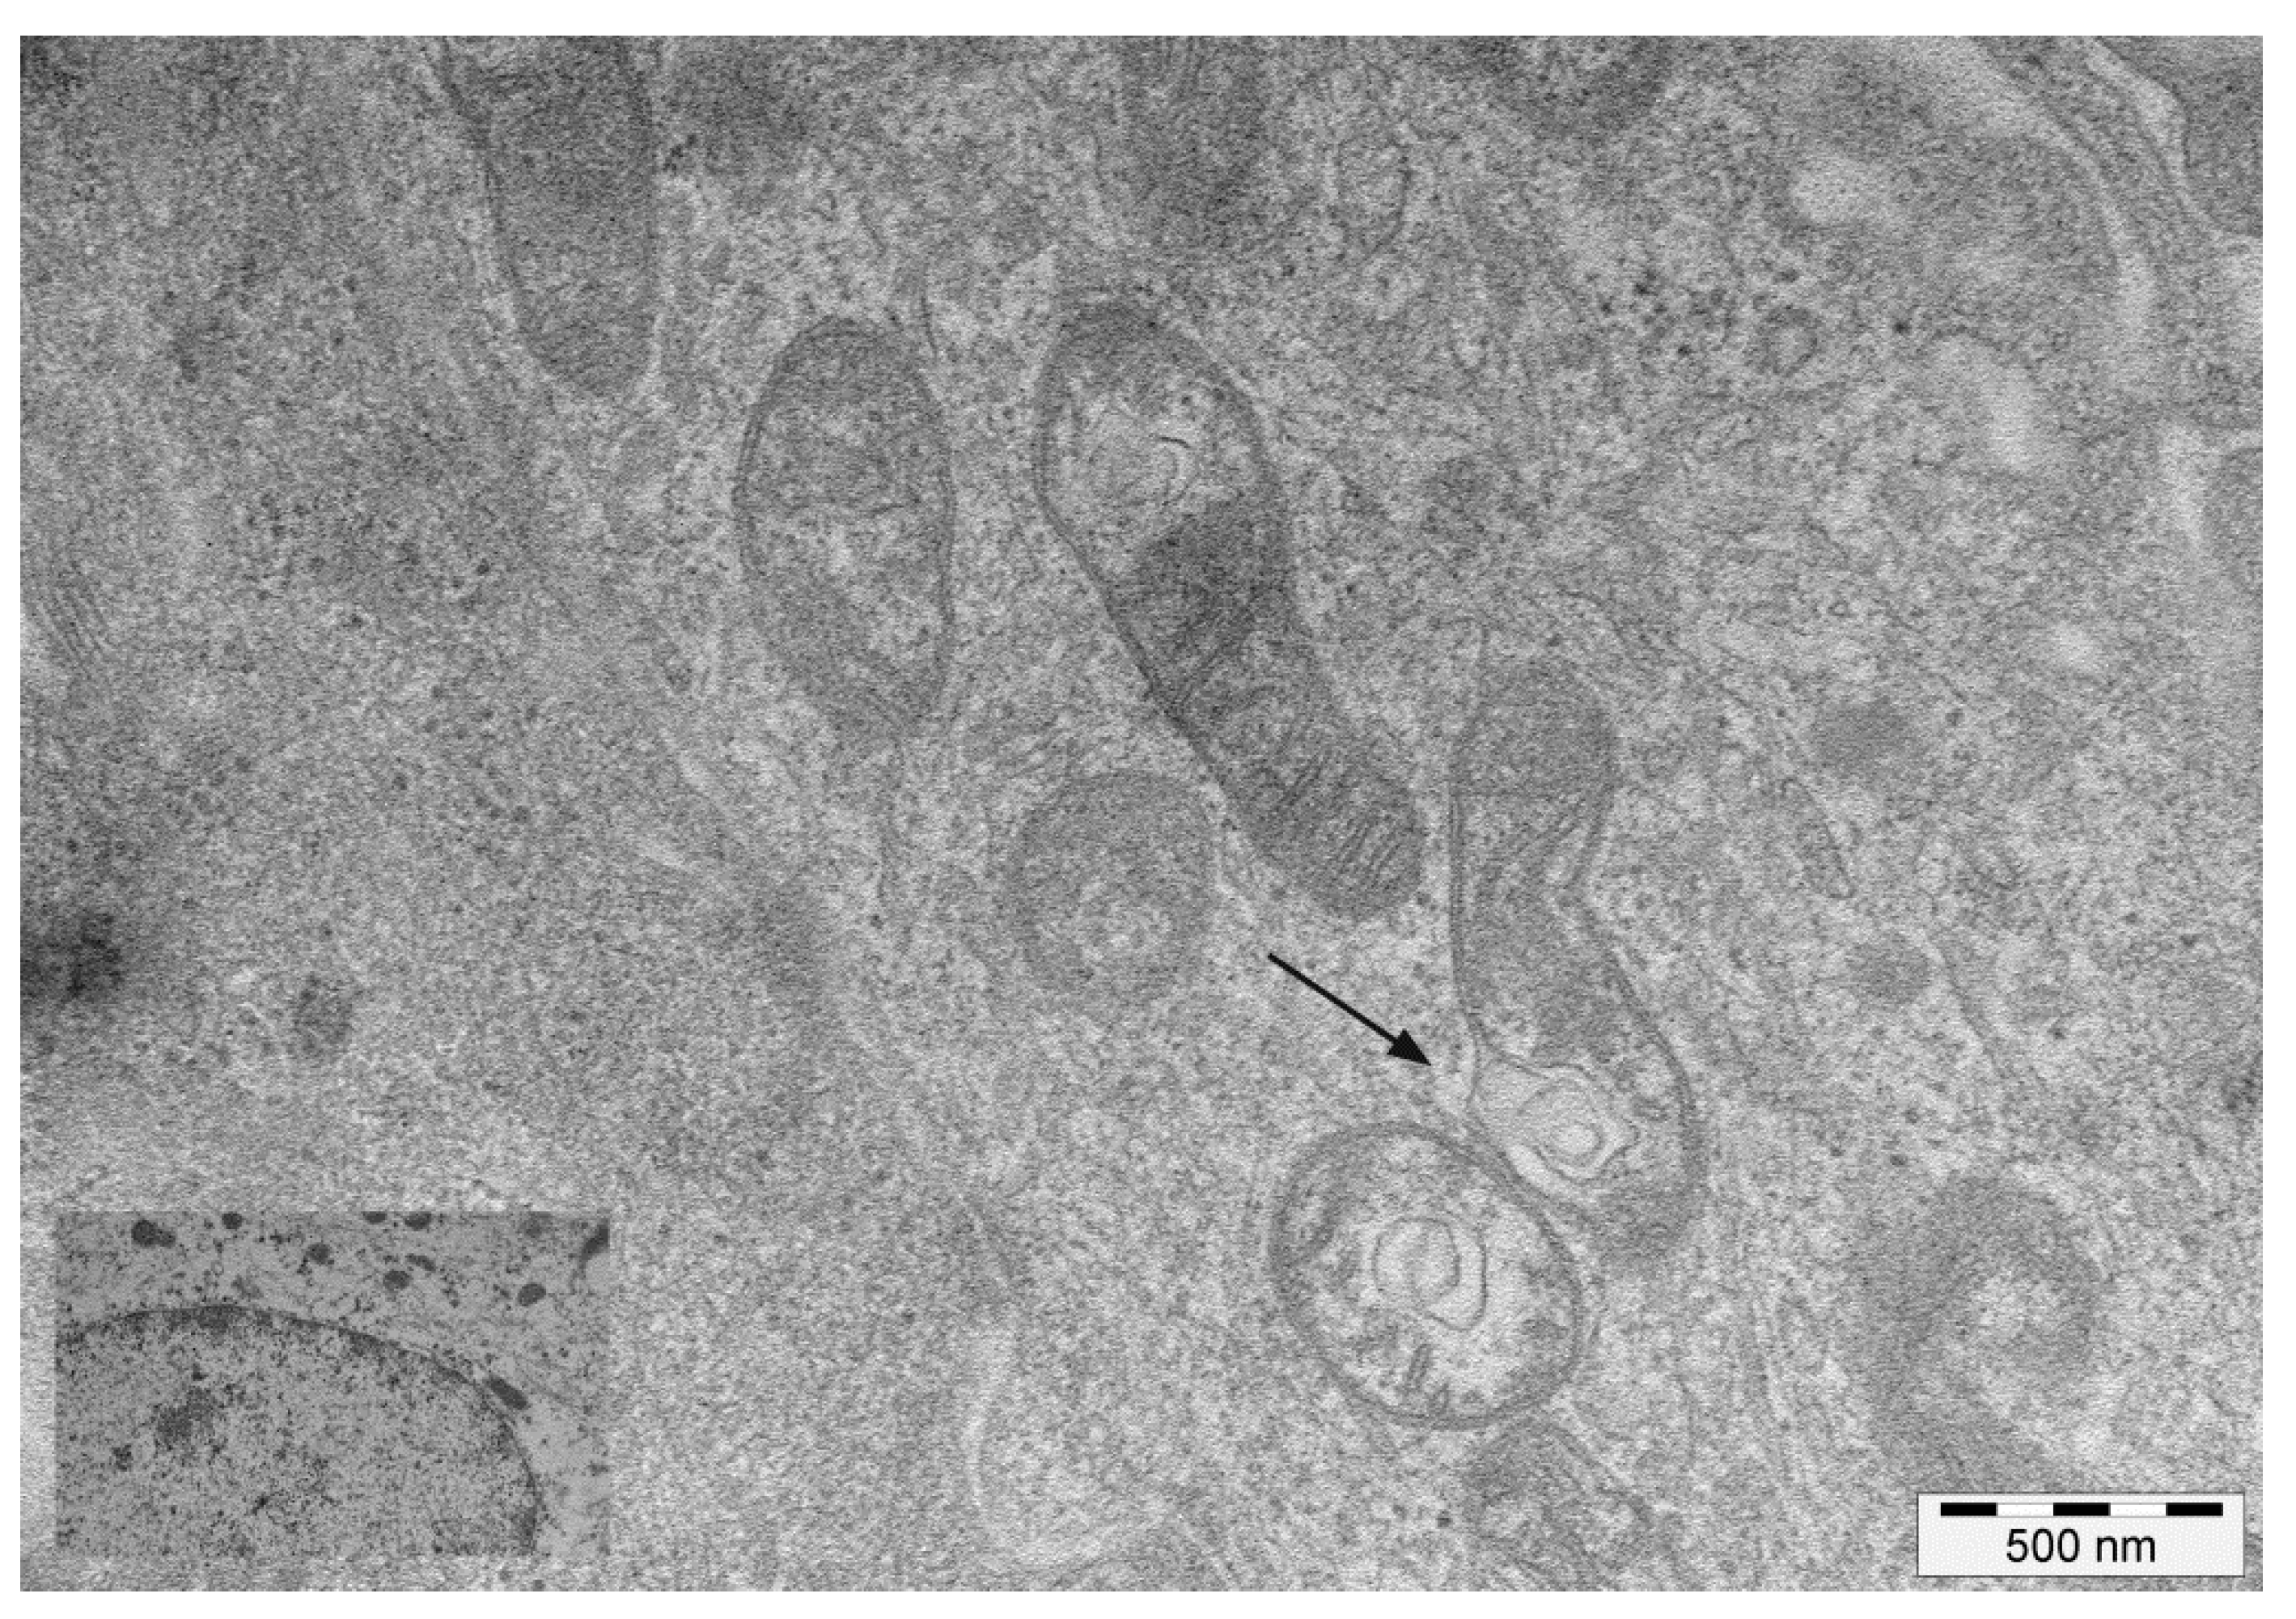

3.1. Virological and Ultrastructural Findings